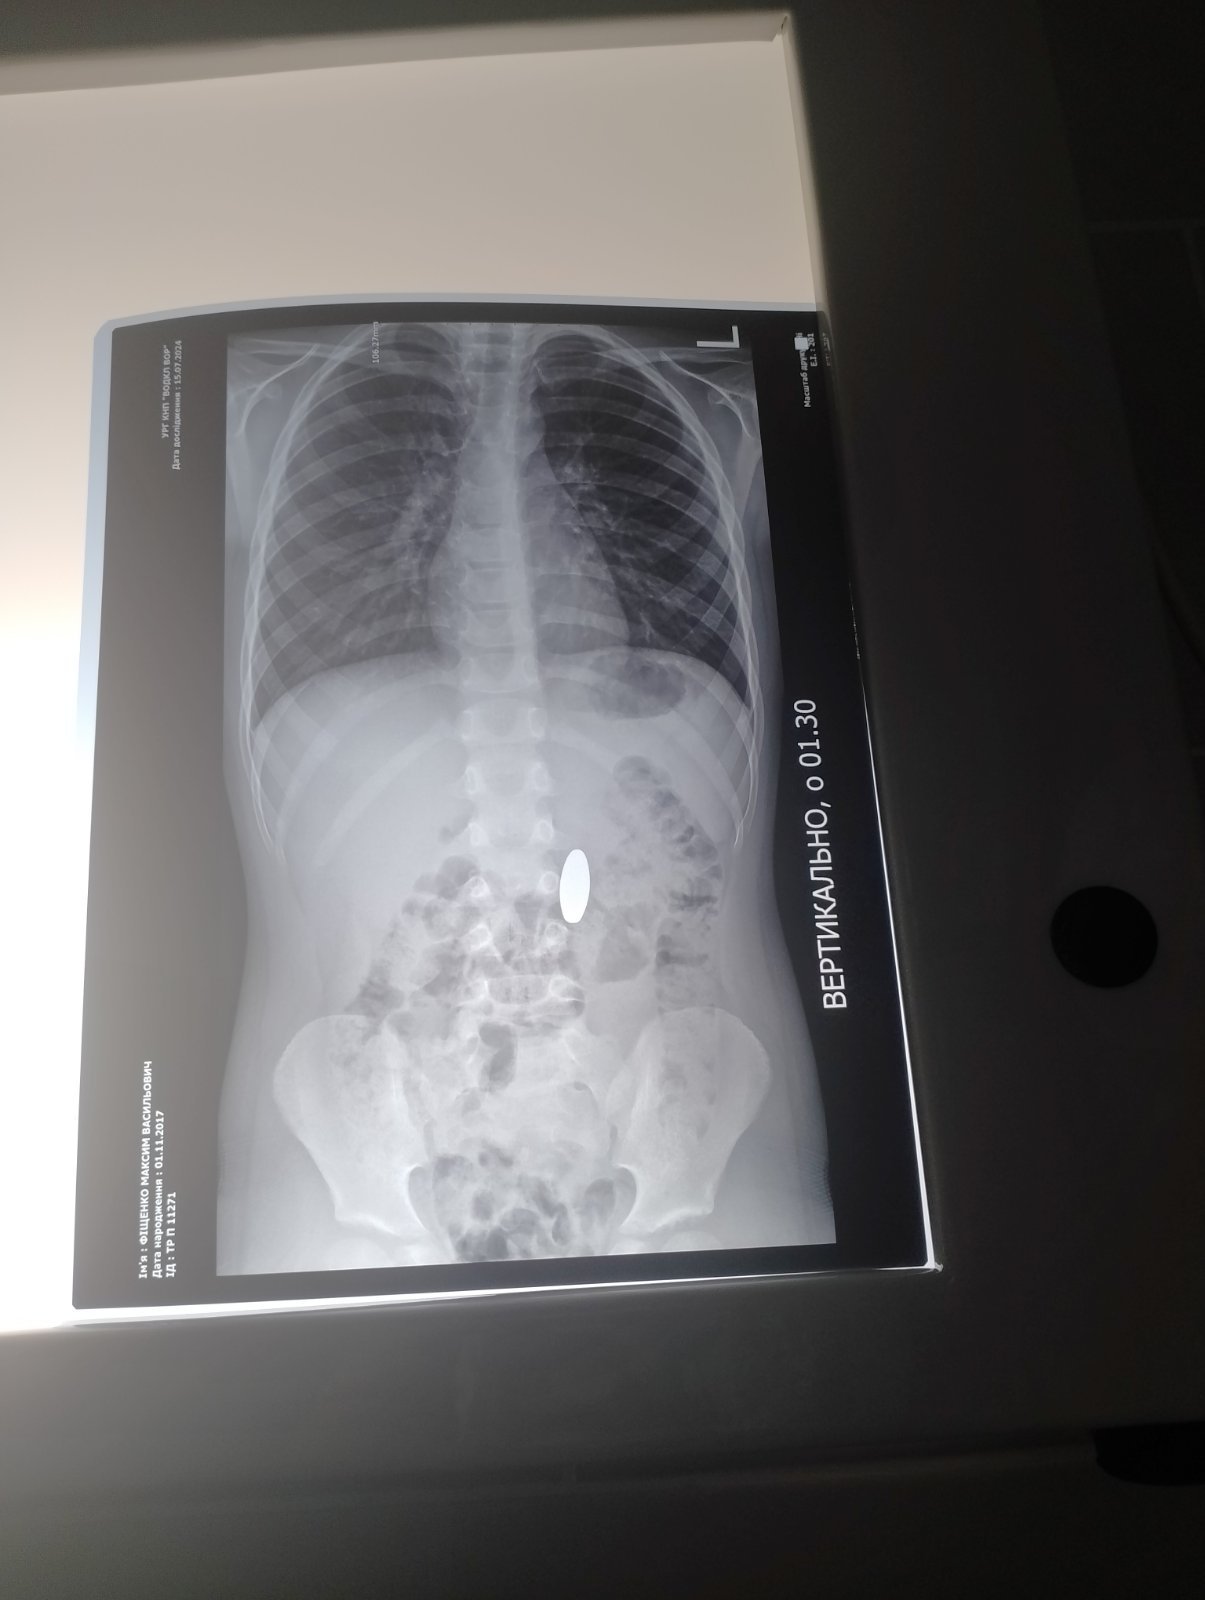

17 липня до Вінницької обласної дитячої клінічної лікарні надійшли чотири звернення через сторонні тіла у шлунково-кишковому тракті дітей віком від 3 до 10 років.

«Лікар-ендоскопіст дитячої обласної лікарні Артур Москаль зазначив, що всі випадки сталися після 23:00, коли діти проковтнули сторонні предмети. Особливу небезпеку становлять магніти, батарейки, монети та дрібні прикраси», - йдеться у повідомленні.